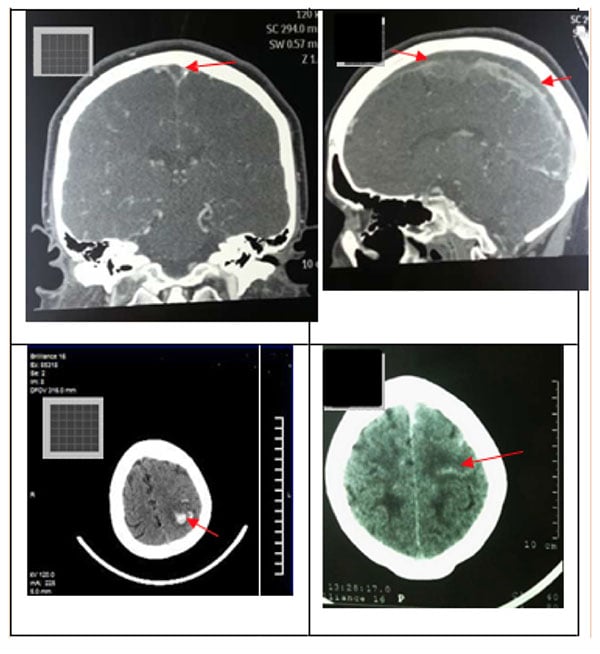

En este caso, la pérdida visual fue refractaria al tratamiento médico y quirúrgico. El papiledema provoca atrofia óptica y ceguera. El retraso en el diagnóstico de TSVD es común. La alta sospecha clínica es obligatoria para un diagnóstico temporano. En este análisis, el tiempo medio transcurrido entre los síntomas clínicos iniciales y el diagnóstico definitivo fue de 9 días. Se prefiere el uso de VTC para hacer el diagnóstico definitivo porque está disponible rápidamente y tiene una alta sensibilidad y especificidad para identificar el seno venoso afectado. La VTC es similar a MRV en el diagnóstico de TSVD [15]. La TC se usa comúnmente como prueba de neuroimagen inicial en pacientes con un diagnóstico clínico de TSVD. La TC cerebral sin contraste suele ser normal, pero puede tener hallazgos que sugieran TSVD [16], por ejemplo, la hiperatenuación de un seno dural. La hiperatenuación en los senos durales en las tomografías computarizadas de cerebro sin contraste tiene una alta precisión en la detección de trombosis sinusal cerebral aguda. Refleja un trombo recién formado [17]. La figura No.2 muestra algunos hallazgos sobre la tomografía computarizada del cerebro sin contraste y la VTC en nuestro análisis. La figura No. 3 muestra la relación entre una TC sin contraste y la RM en un caso de infarto venoso.

Figura No. 2. Principales hallazgos en la tomografía computarizada cerebral sin contraste VTC. A (coronal) y B (sagital) muestra un defecto de llenado extenso en el SSS secundario a un coágulo (flechas, paciente No. 6). C la TC (axial, sin medio de contraste) muestra una hemorragia parenquimatosa parietal izquierda (paciente nº 5). Este caso tuvo un SSS ocluido y dejó el ST. D (axial, sin medio de contraste) hiperdensidad lineal en el lóbulo parietal cortical izquierdo secundaria a un coágulo en una vena cortical ("signo de cordón", flecha) (paciente No. 8). Este caso tenía un SSS ocluido.